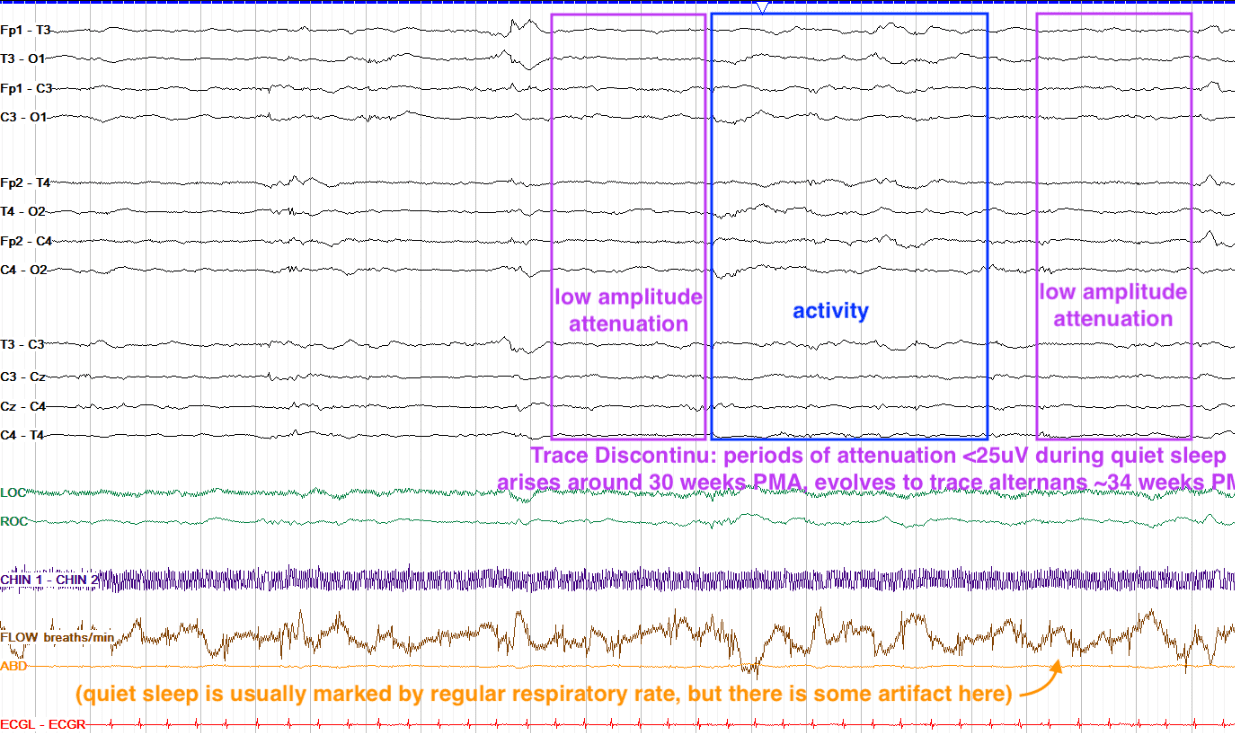

Quiet sleep is characterized by the eyes being closed with minimal eye movements and regular respirations. Generally, neonates move from awake into active sleep, then into quiet sleep. Quiet sleep is marked by a pattern known as trace discontinu (attenuated periods <25μV) from 30-34 weeks PMA and by trace alternans (attenuated periods >25μV). Starting at 34 weeks PMA, trace discontinu evolves into trace alternans, in which interburst intervals are higher amplitude — 25μV or more and in turn the IBI continues to shorten. Beginning as early as 34 weeks onward to term, trace alternans evolves to slow wave sleep.